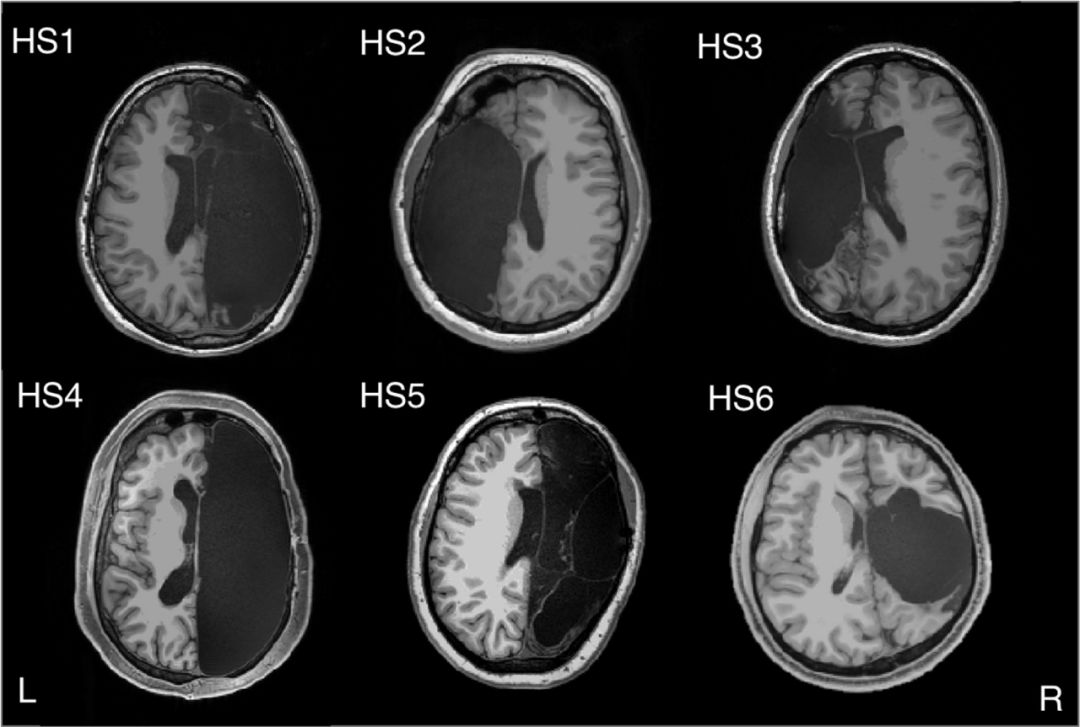

只剩一半大脑会怎样?6个罕见病例首次揭示:半个大脑也能"全职"工作